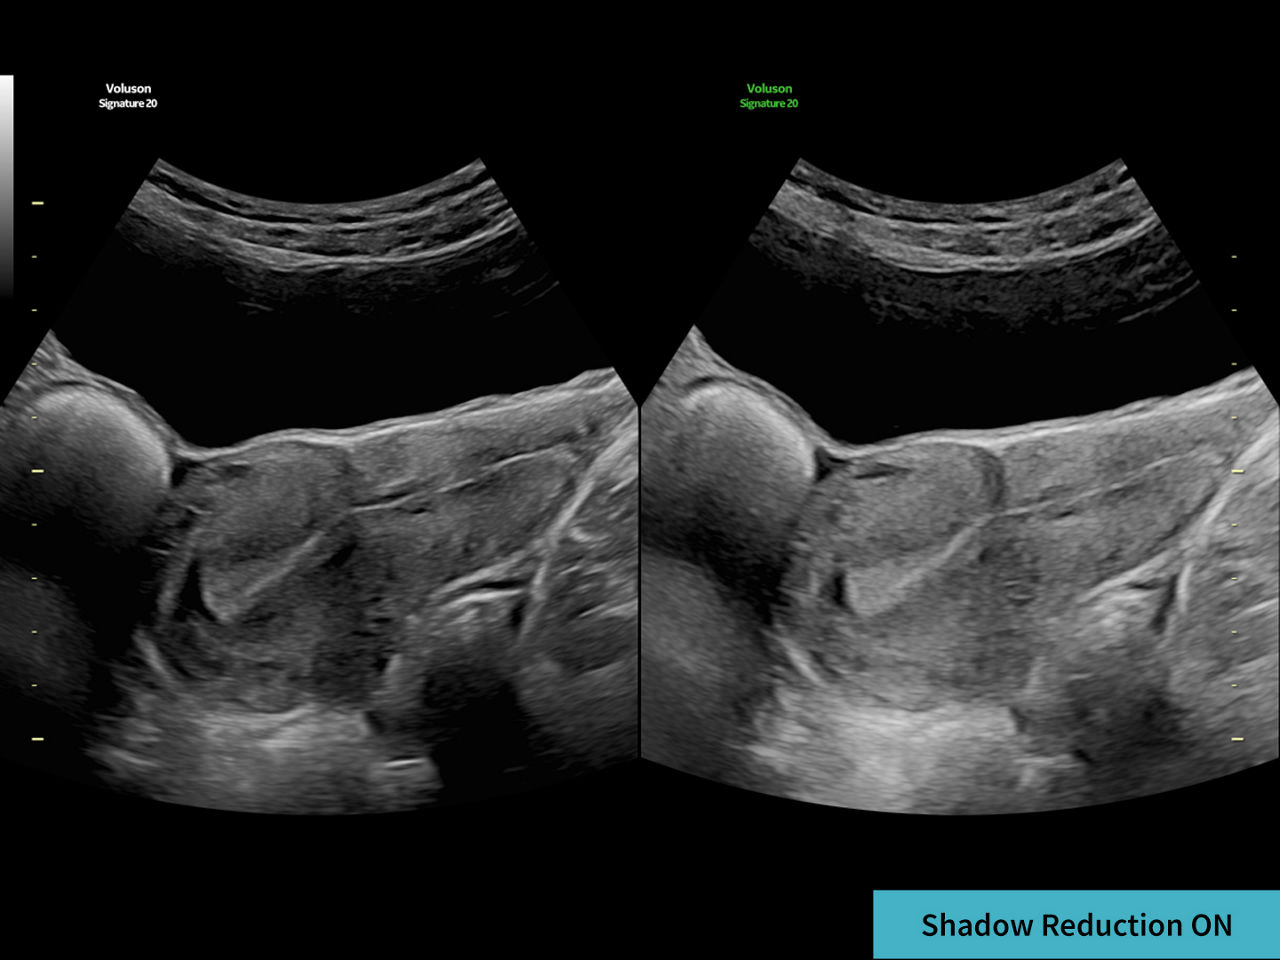

Restore tissue information and borders

Decreases shadows on B-mode imaging which can obscure adjacent structures by helping to restore tissue information and borders.

3-augment-image